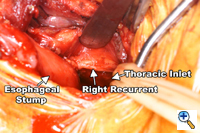

Dissection of the "third-field" begins during the thoracic portion of the procedure and is later completed through a collar neck incision. Dissection of the nodes in the superior mediastinum includes the nodes along the right and left recurrent laryngeal nerves throughout their mediastinal course. The paratracheal retrocaval compartment is not disturbed. The left recurrent nerve is dissected using a "no-touch" technique and nodes along its anterior aspect are carefully excised (Figure 3). Notably, there is a paucity of nodal tissue along the left nerve in nearly all Caucasians. The right recurrent nerve is carefully exposed near its origin at the base of the right subclavian artery. The right recurrent nodal chain begins at that level and forms a continuous package that extends through the thoracic inlet to the neck. Again, the nerve is dissected using a strict "no-touch" technique (Figure 4). Through the cervical incision, the remainder of the recurrent nodes are dissected as are the lower deep cervical nodes located posterior and lateral to the carotid sheath. Thus the "third-field" includes a continuous anatomically inseparable chain of nodes that extends from the superior mediastinum to the lower neck. These nodes should be appropriately labeled cervicothoracic (CT) nodes rather than cervical nodes.

A generous low collar incision is performed and subplatysmal flaps are raised inferiorly and superiorly. The strap muscles and the medial heads of the sternocleidomastoid are divided. The esophagus (previously fully mobilized from the thorax) is retrieved from the prevertebral space. The esophagus is divided distally and the specimen is retrieved in the abdomen. The previously dissected recurrent nerves are easy to visualize (especially the right recurrent) and any residual nodal tissue is excised (Figure 6). Next, the nodes posterior and lateral to the carotid sheath are removed along with the supraclavicular nodes (Figure 7). The dissection is limited superiorly by the inferior belly of the omohyoid. Within the abdomen the gastric tube is prepared and the specimen is removed (Figure 8). Gastrointestinal continuity is restored by a cervical esophagogastrostomy.